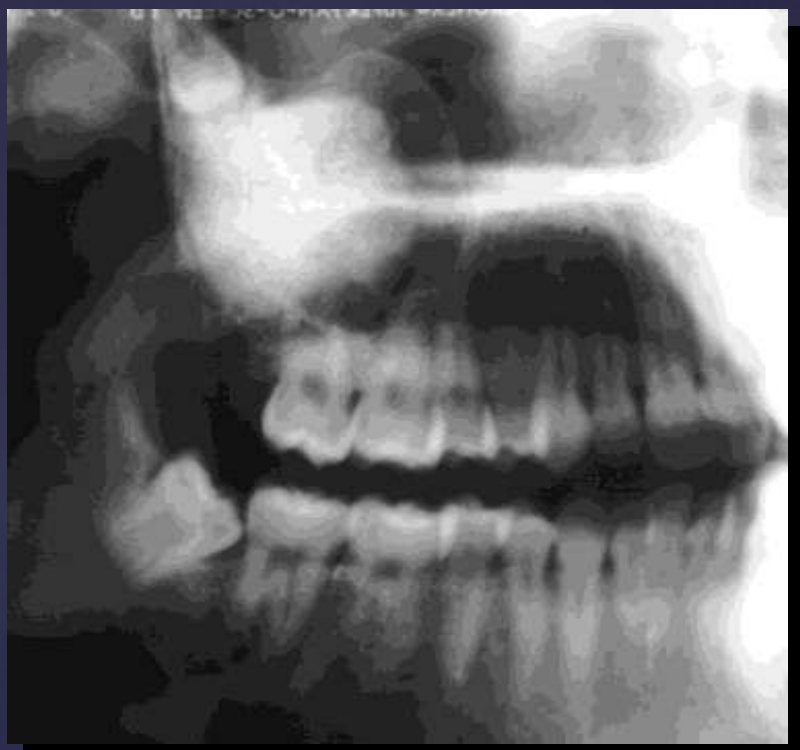

ameloblastoma

Pericoronal/mural; impacted tooth

Displacement of #32

Osseous expansion

Thinning of cortices

Displacement of inferior alveolar nerve canal

Multilocular

Root resorption

Thinning of inferior mandibular border

Septae appear coarse

Displacement of teeth